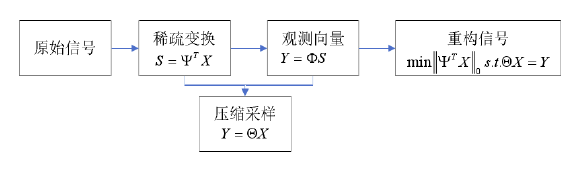

因此我们需要有关于真实图像的一些先验信息,再通过优化的方法去获得一个最优解,这类方法我们可以称之为传统方法。这其中比较著名的理论是压缩感知理论,处理流程如图4所示【1】。而我们经常使用到先验信息有:(1)图像在某一变换域内的稀疏性,如DCT,小波,TV,对应的是  范数以及它的凸近似替代

范数以及它的凸近似替代  范数;(2)图像的低秩性,对应的是核范数

范数;(2)图像的低秩性,对应的是核范数  ;(3)图像的非局部自相似性,即在一幅图像中,相似的纹理或结构会多次出现。

;(3)图像的非局部自相似性,即在一幅图像中,相似的纹理或结构会多次出现。